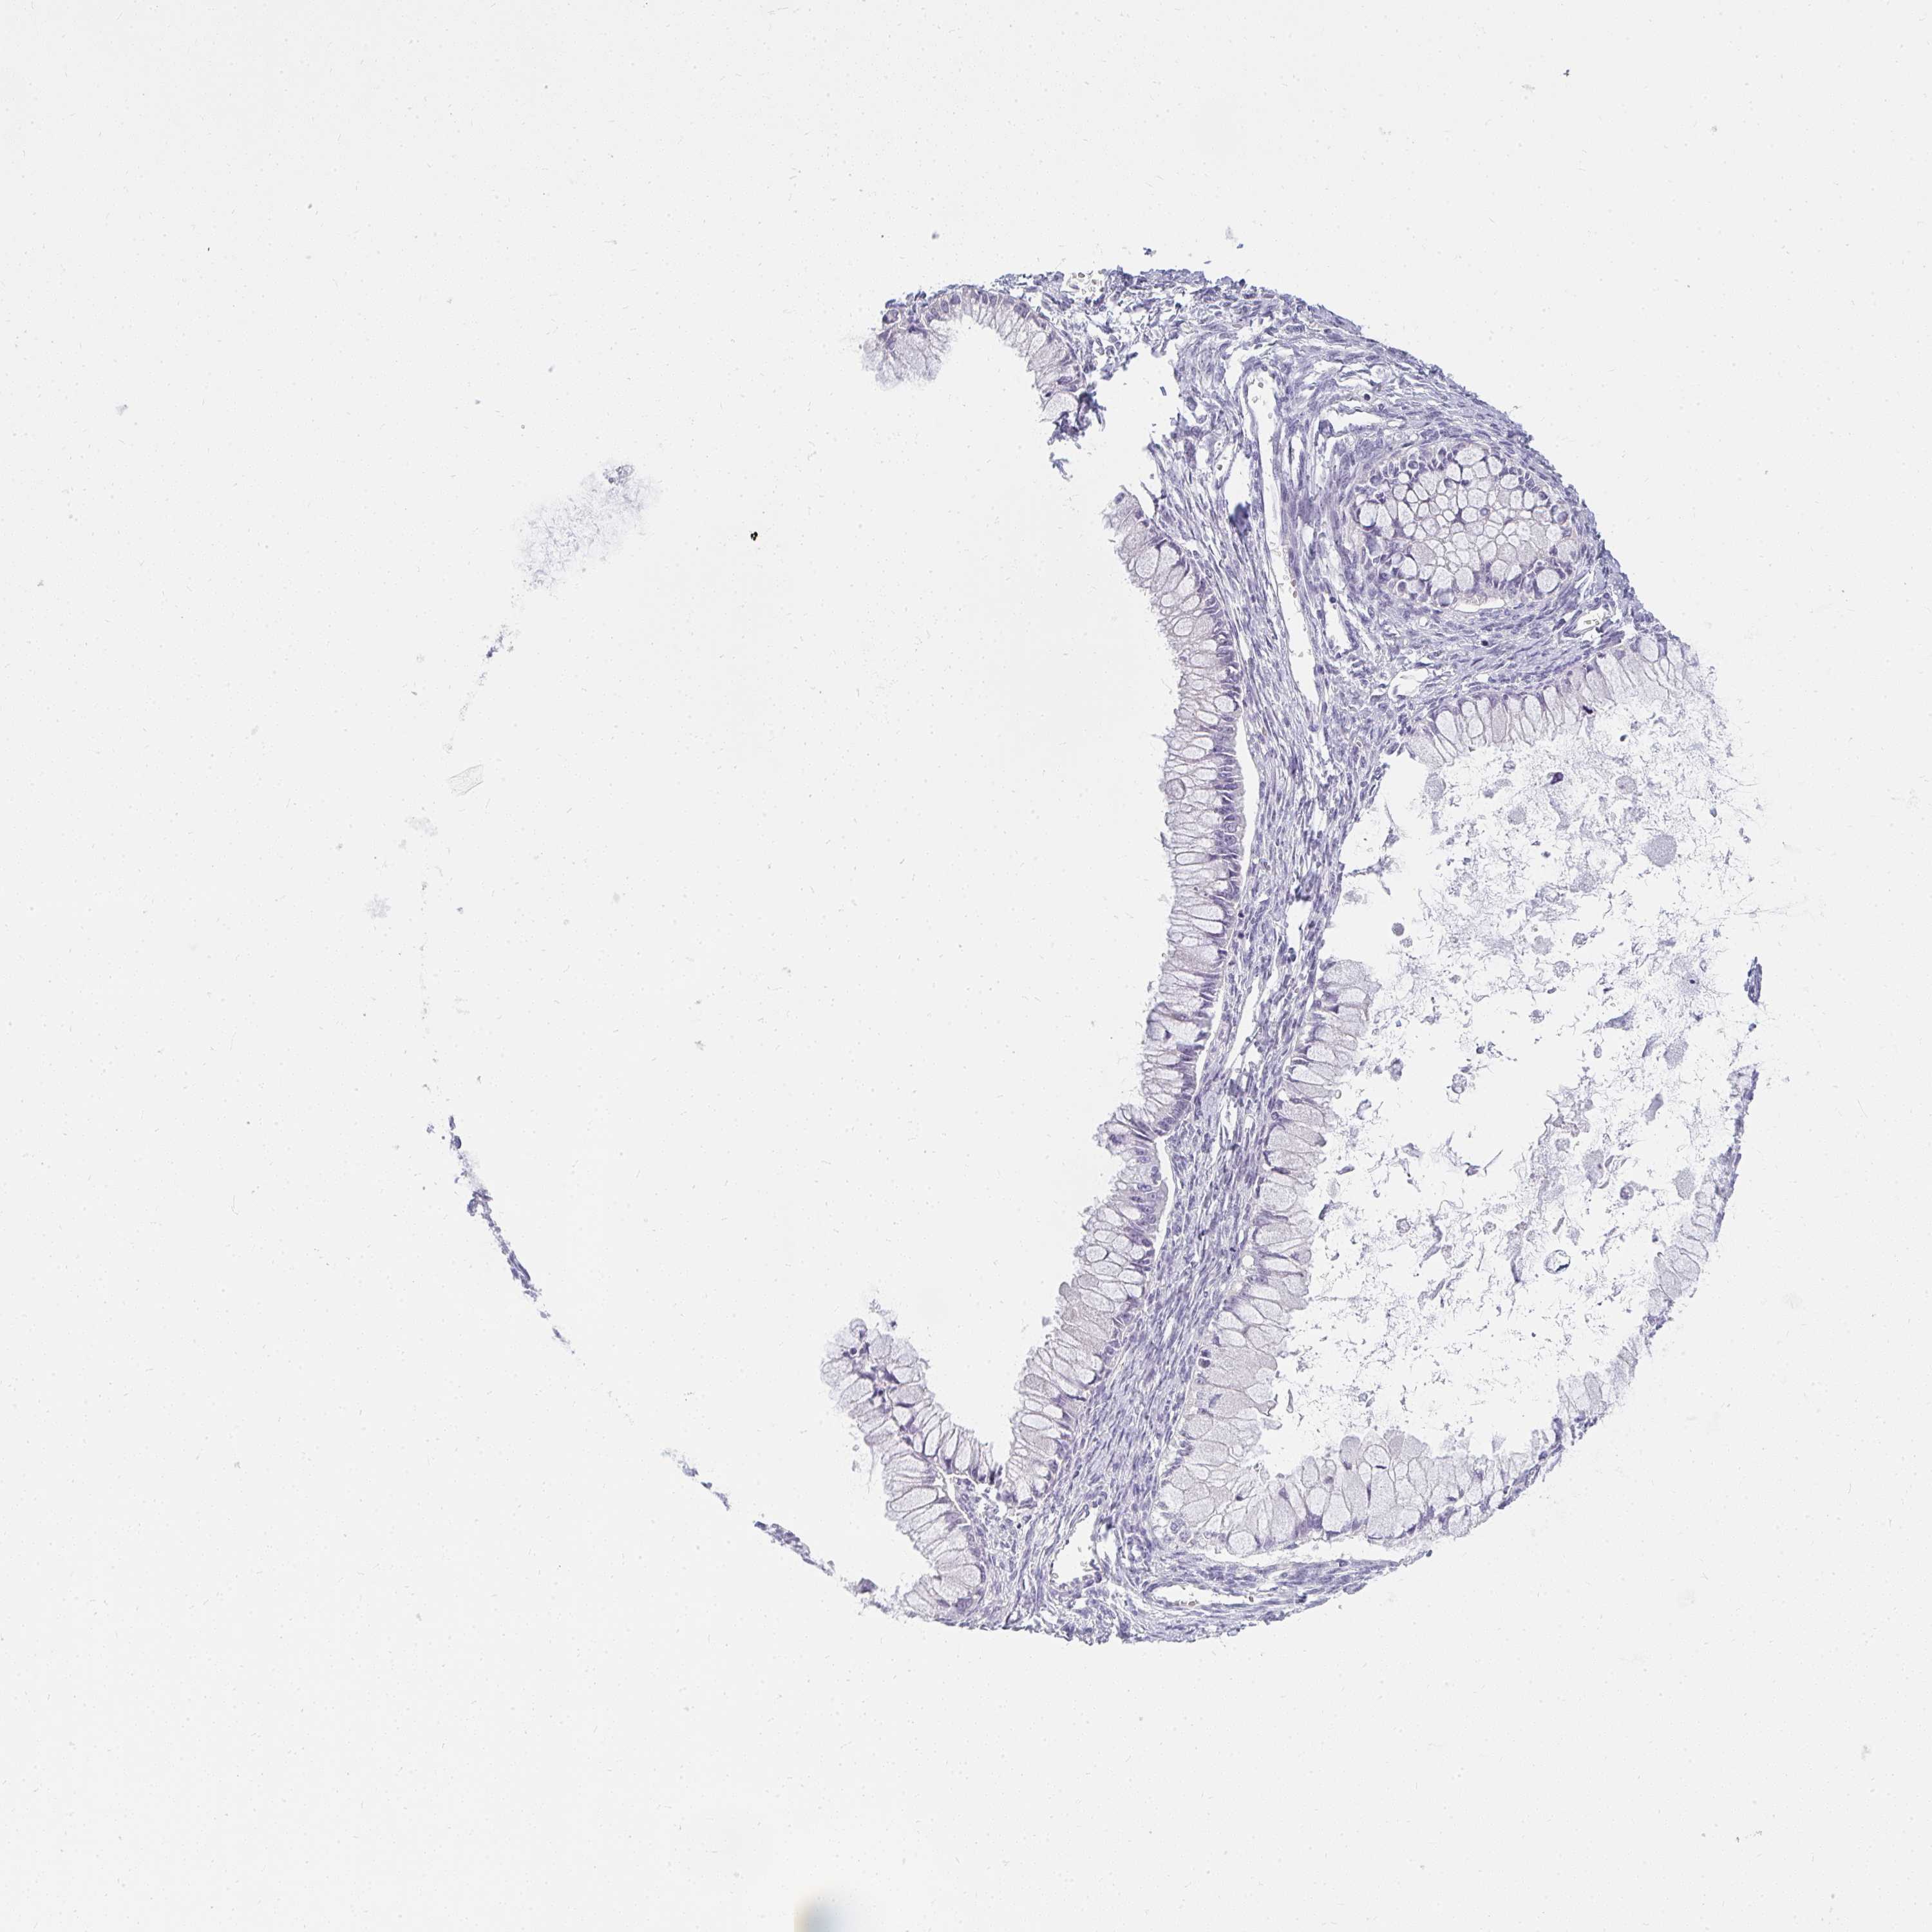

OVARIAN CANCER - Protein expressioni

A mouse-over function shows sample information and annotation data. Click on an image to view it in a full screen mode. Samples can be filtered based on level of antibody staining by selecting one or several of the following categories: high, medium, low and not detected. The assay and annotation is described here.

Note that samples used for immunohistochemistry by the Human Protein Atlas do not correspond to samples in the TCGA dataset.

Antibody stainingi

Antibody staining in the annotated cell types in the current human tissue is reported as not detected, low, medium, or high, based on conventional immunohistochemistry profiling in selected tissues. This score is based on the combination of the staining intensity and fraction of stained cells.

Each image is clickable and will lead to virtual microscopy that enables deeper exploration of all samples and also displays staining intensity scores, fraction scores and subcellular localization as well as patient and tissue information for each sample.

Antibody HPA056393

Staining

High

Medium

Low

Not detected

Intensity

Strong

Moderate

Weak

Negative

Quantity

>75%

75%-25%

<25%

None

Location

Nuclear

Cytoplasmic/membranous

Cytoplasmic/membranous,nuclear

Cystadenocarcinoma, serous, NOS

Cystadenocarcinoma, mucinous, NOS

Carcinoma, endometroid